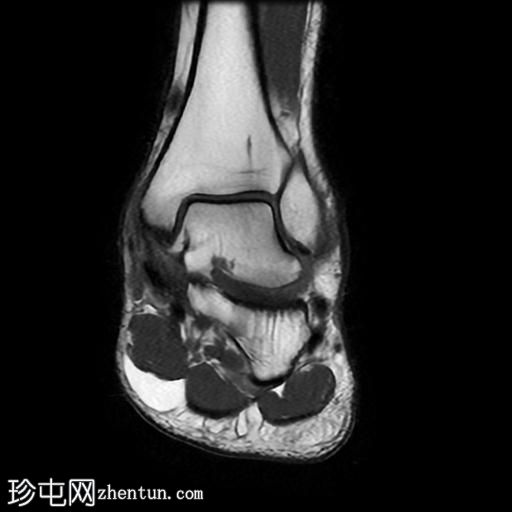

MRI

矢状位

PD脂肪抑制序列

冠状位

T1加权像

冠状位PD脂肪抑制序列

轴位

T2加权像

跟骨前突延长增宽,与舟骨形成不规则关节,形似“食蚁兽

鼻

”。

该异常跟舟关节处可见关节下骨髓水肿。此外,舟骨内外侧径增宽,向外侧逐渐变细,并与增大的跟骨前突形成关节。

距舟关节轻度积液,并可见边缘骨赘。